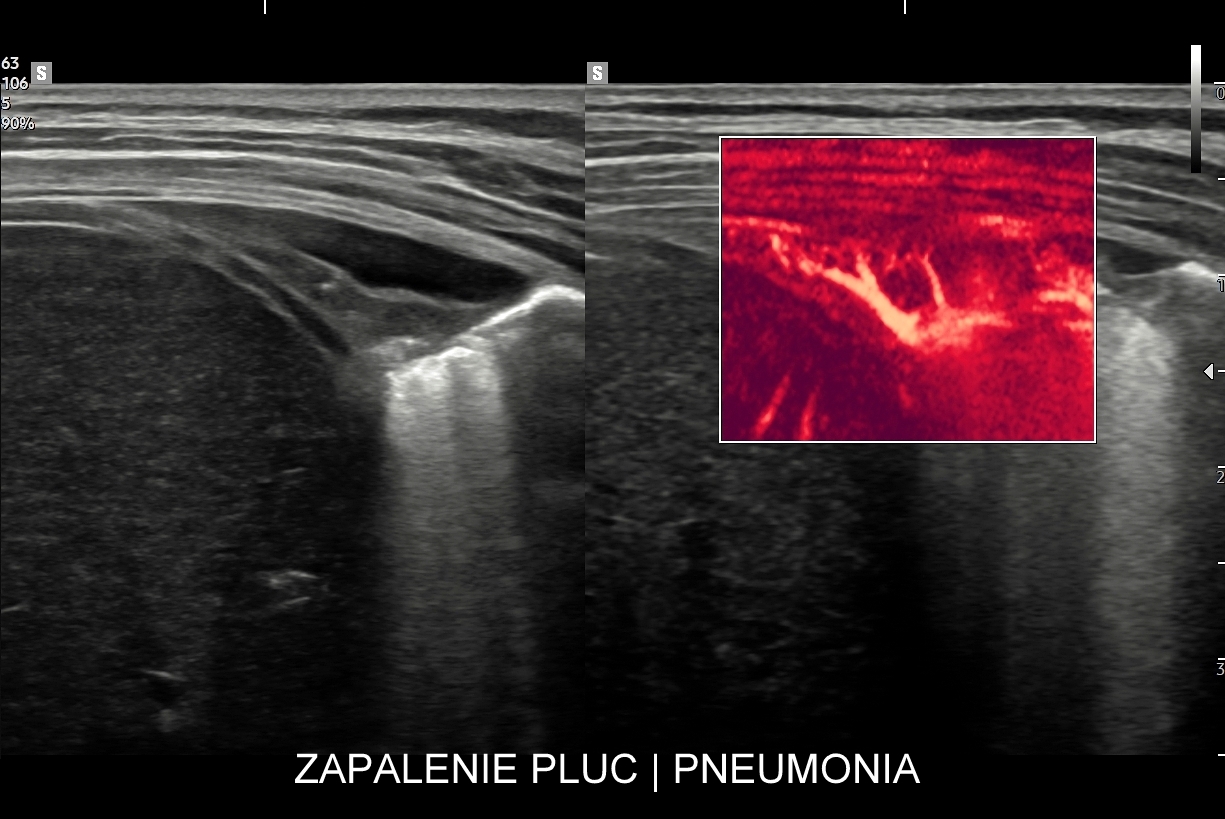

Kluczem do wartościowego zastosowania metody USG w diagnostyce pulmonologicznej jest zrozumienie jej możliwości oraz ograniczeń. USG jest niezwykle czułym badaniem w diagnostyce zapaleń płuc zarówno płatowych, jak i atypowych, np. wywołanych przez Mycoplasma lub Chlamydia. W przypadku zapalenia płuc pojawienie się widocznych zmian sonograficznych wyprzedza wystąpienie fenomenów osłuchowych wykrywanych przy osłuchiwaniu klasycznym stetoskopem. Metoda USG jest również bardzo czuła w diagnostyce chorób opłucnej i jam opłucnowych, takich jak nowotwory opłucnej, odma odma opłucnowa czy płyn w jamie opłucnowej. W rękach doświadczonego lekarza badanie USG może być przydatne w wykryciu zatorowości płucnej, a nawet guzów nowotworowych płuc.

Specjalista chorób wewnętrznych. Absolwent Akademii Medycznej we Wrocławiu w 2000 r. Zwolennik nowoczesnych technologii i pionier niestandardowych zastosowań USG w Polsce, w tym użycia obrazowania mikroprzepływów w obrazowaniu płuc, czy badań USG z kontrastem. Na początku lat 2000-ych był jednym z pierwszych lekarzy, który wdrażali szerokie zastosowanie USG w intensywnej terapii. W praktyce ambulatoryjnej wprowadził do regularnego użycia kompleksowe badanie USG klatki piersiowej, płuc i serca. Posiada wieloletni staż kliniczny i szkoleniowy w Polsce oraz zagranicą (Wielka Brytania, Niemcy, Austria, Włochy, Rumunia). Wykonał ponad 40.000 badań USG. Dydaktyk i nauczyciel młodego pokolenia lekarzy w Polsce i Europie.